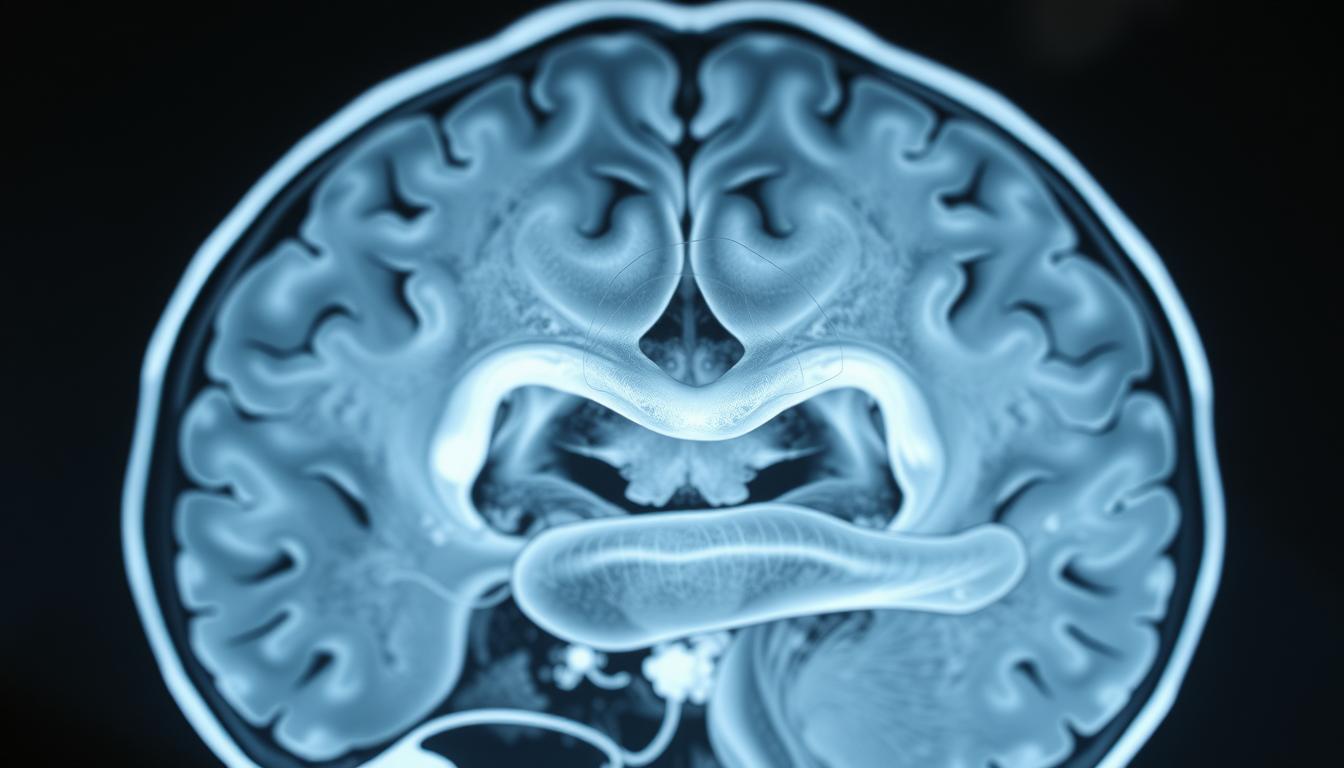

Le principe de l’IRM repose sur la détection des atomes d’hydrogène présents dans les molécules d’eau du corps. Ces atomes réagissent au champ magnétique, permettant de créer des images précises des organes internes. Cette méthode est particulièrement utile pour examiner le cerveau, le cœur ou les tumeurs, offrant ainsi des informations essentielles pour le diagnostic et le traitement.

L’IRM à champ fermé utilise un aimant cylindrique pour générer un champ magnétique puissant. Ce modèle est idéal pour obtenir des images de haute résolution, notamment pour les structures complexes comme le cerveau. Cependant, certains patients peuvent ressentir une sensation d’enfermement due à l’espace restreint.

L’IRM fonctionnelle est une méthode révolutionnaire pour explorer le cerveau. Elle permet d’observer l’activité cérébrale en temps réel, offrant des insights précieux sur les connexions neuronales et les fonctions cognitives. Cette technique est largement utilisée en neurosciences pour étudier des phénomènes complexes comme la mémoire, l’attention et les émotions.

L’IRM fonctionnelle repose sur la détection des variations du flux sanguin dans le cerveau. Lorsqu’une région cérébrale est active, elle consomme plus d’oxygène, ce qui modifie le signal magnétique capté par l’appareil. Ces données sont ensuite transformées en cartes d’activité cérébrale.

Le projet NeuroSpin du CEA Saclay utilise une IRM 11.7 Tesla pour étudier les réseaux neuronaux au repos. Cette technologie permet de visualiser les interactions entre différentes zones du cerveau, même en l’absence de stimuli externes.

- Le cerveau : détection de tumeurs, accidents vasculaires cérébraux (AVC).